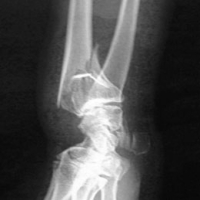

Classifications des Fractures de l'extrémité distale du Radius :

Selon l'inclinaison de la surface articulaire :

Sur un cliché de profil :

- Fracture en extension (déplacement postérieur de la surface articulaire, inversion de la pente radiale)

- Fracture en flexion, déplacement antérieur, accentuation de la pente (Nle 10 à 14°)

Sur un cliché de face :

Déplacement en dehors (désaxation en baillonnette)

Altération de l'inclinaison radiale (23°)

Classification topographique :

1/ Fracture extra-articulaire :

- en extension (Colles, Pouteau-Colles),  avec déformation en dos de fourchette

- en flexion (Smith type 1, Goyrand). On distingue 3 types de Fracture de Smith en fonction de l'obliquité du trait de fracture; les types 2 (irradiation plus dorsale du trait que dans le type 3) et 3 (identique au reverse Barton) sont instables. La fracture de Smith qui résulte d'un choc sur la face dorsale du poignet est responsable d'un déplacement ventral du fragment distal (déformation en ventre de cuillère).

2/ Fracture articulaire partielle :

- fracture de la styloïde radiale ou Fracture de Hutchinson ou de Chauffeur (instable, souvent combinée à une fracture ou une luxation du carpe)

- en flexion, fréquent, "Reverse Barton", "Smith" type 2, "Letenneur"

- en extension, plus rare, "Barton" (fracture du rebord dorsal du radius)

3/ Fracture Articulaire :

- en T ou en Y. Die punch fracture

- forme particuliére : Fracture de Galeazzi associant une fracture distale du radius parfois s'étendant jusqu'à l'articulation radio-carpienne, et une luxation de l'articulation radio-cubitale inférieure